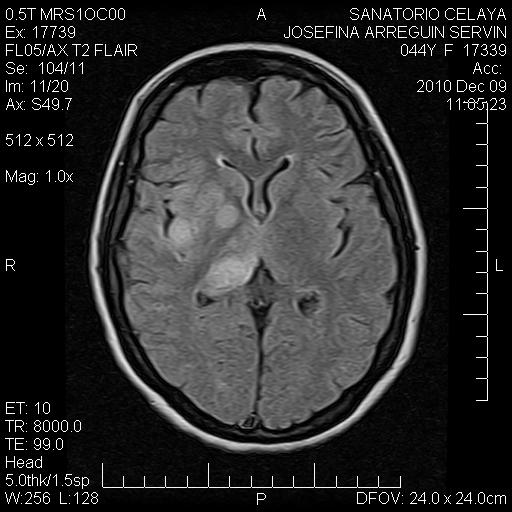

Las imágenes más representativas están aquí,

Se hace notar que la paciente no tiene ni síntomas ni signos de craneo-hipertensivo.